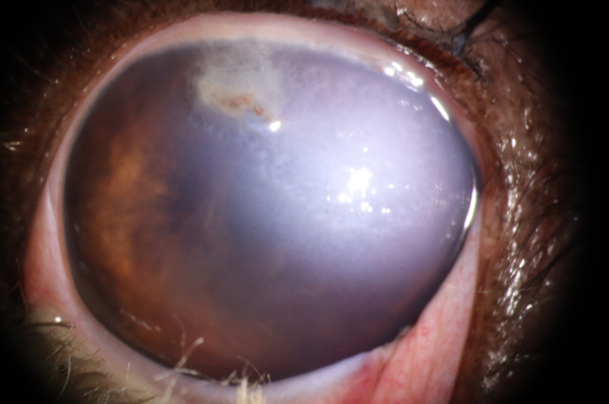

사진 1. 고양이 발톱에 의한 penetrating injury. 결막의 중등도의 충혈 및 부종 확인되며, 천공부위는 fibrin으로 일시적으로 막힘. 천공 부위 주변부 각막의 부종 확인됨. 전안방은 fibrin 및 출혈괴 확인됨. 안방수의 흐림정도는 매우 심하였으며, 홍채는 각막 열린 부분으로 부분 전방 유착 확인됨.